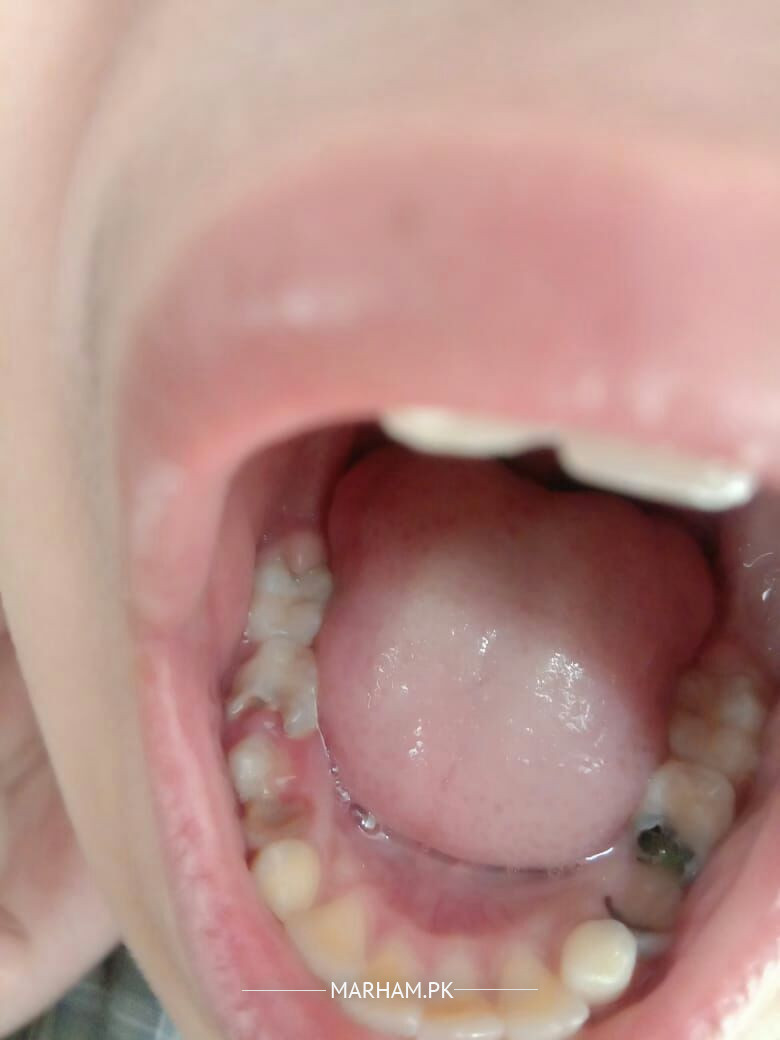

Asking For Brother, Male 11, Lahore

Pain in Teeth's , swelling, facing problem in eating

Duration of complain: 4 days

there are multiple carious teeth in both upper and lower jaw.

visit a dentist As soon as possible for appropriate management

Pain in any specific area? There are many teeth that needs filling . For that you need to visit dentist . Pain and swelling can be due to these carious teeth

Dear concerned as u can see yourself in the picture multiple carious (black) teeth

need to visit dentist for their treatment for sure without any delays

Dear patient I have read your complain. There are multiple carious teeth that need proper evaluation for deciding appropriate treatment planning. For further evaluation book an appointment with Marham. Thanks.